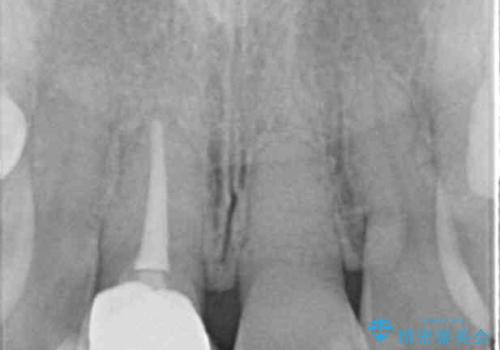

- 歯の神経を除去したのちの、変色の改善を希望され来院されました。

再度根管治療を行ったのちの、オールセラミッククラン治療を計画します。